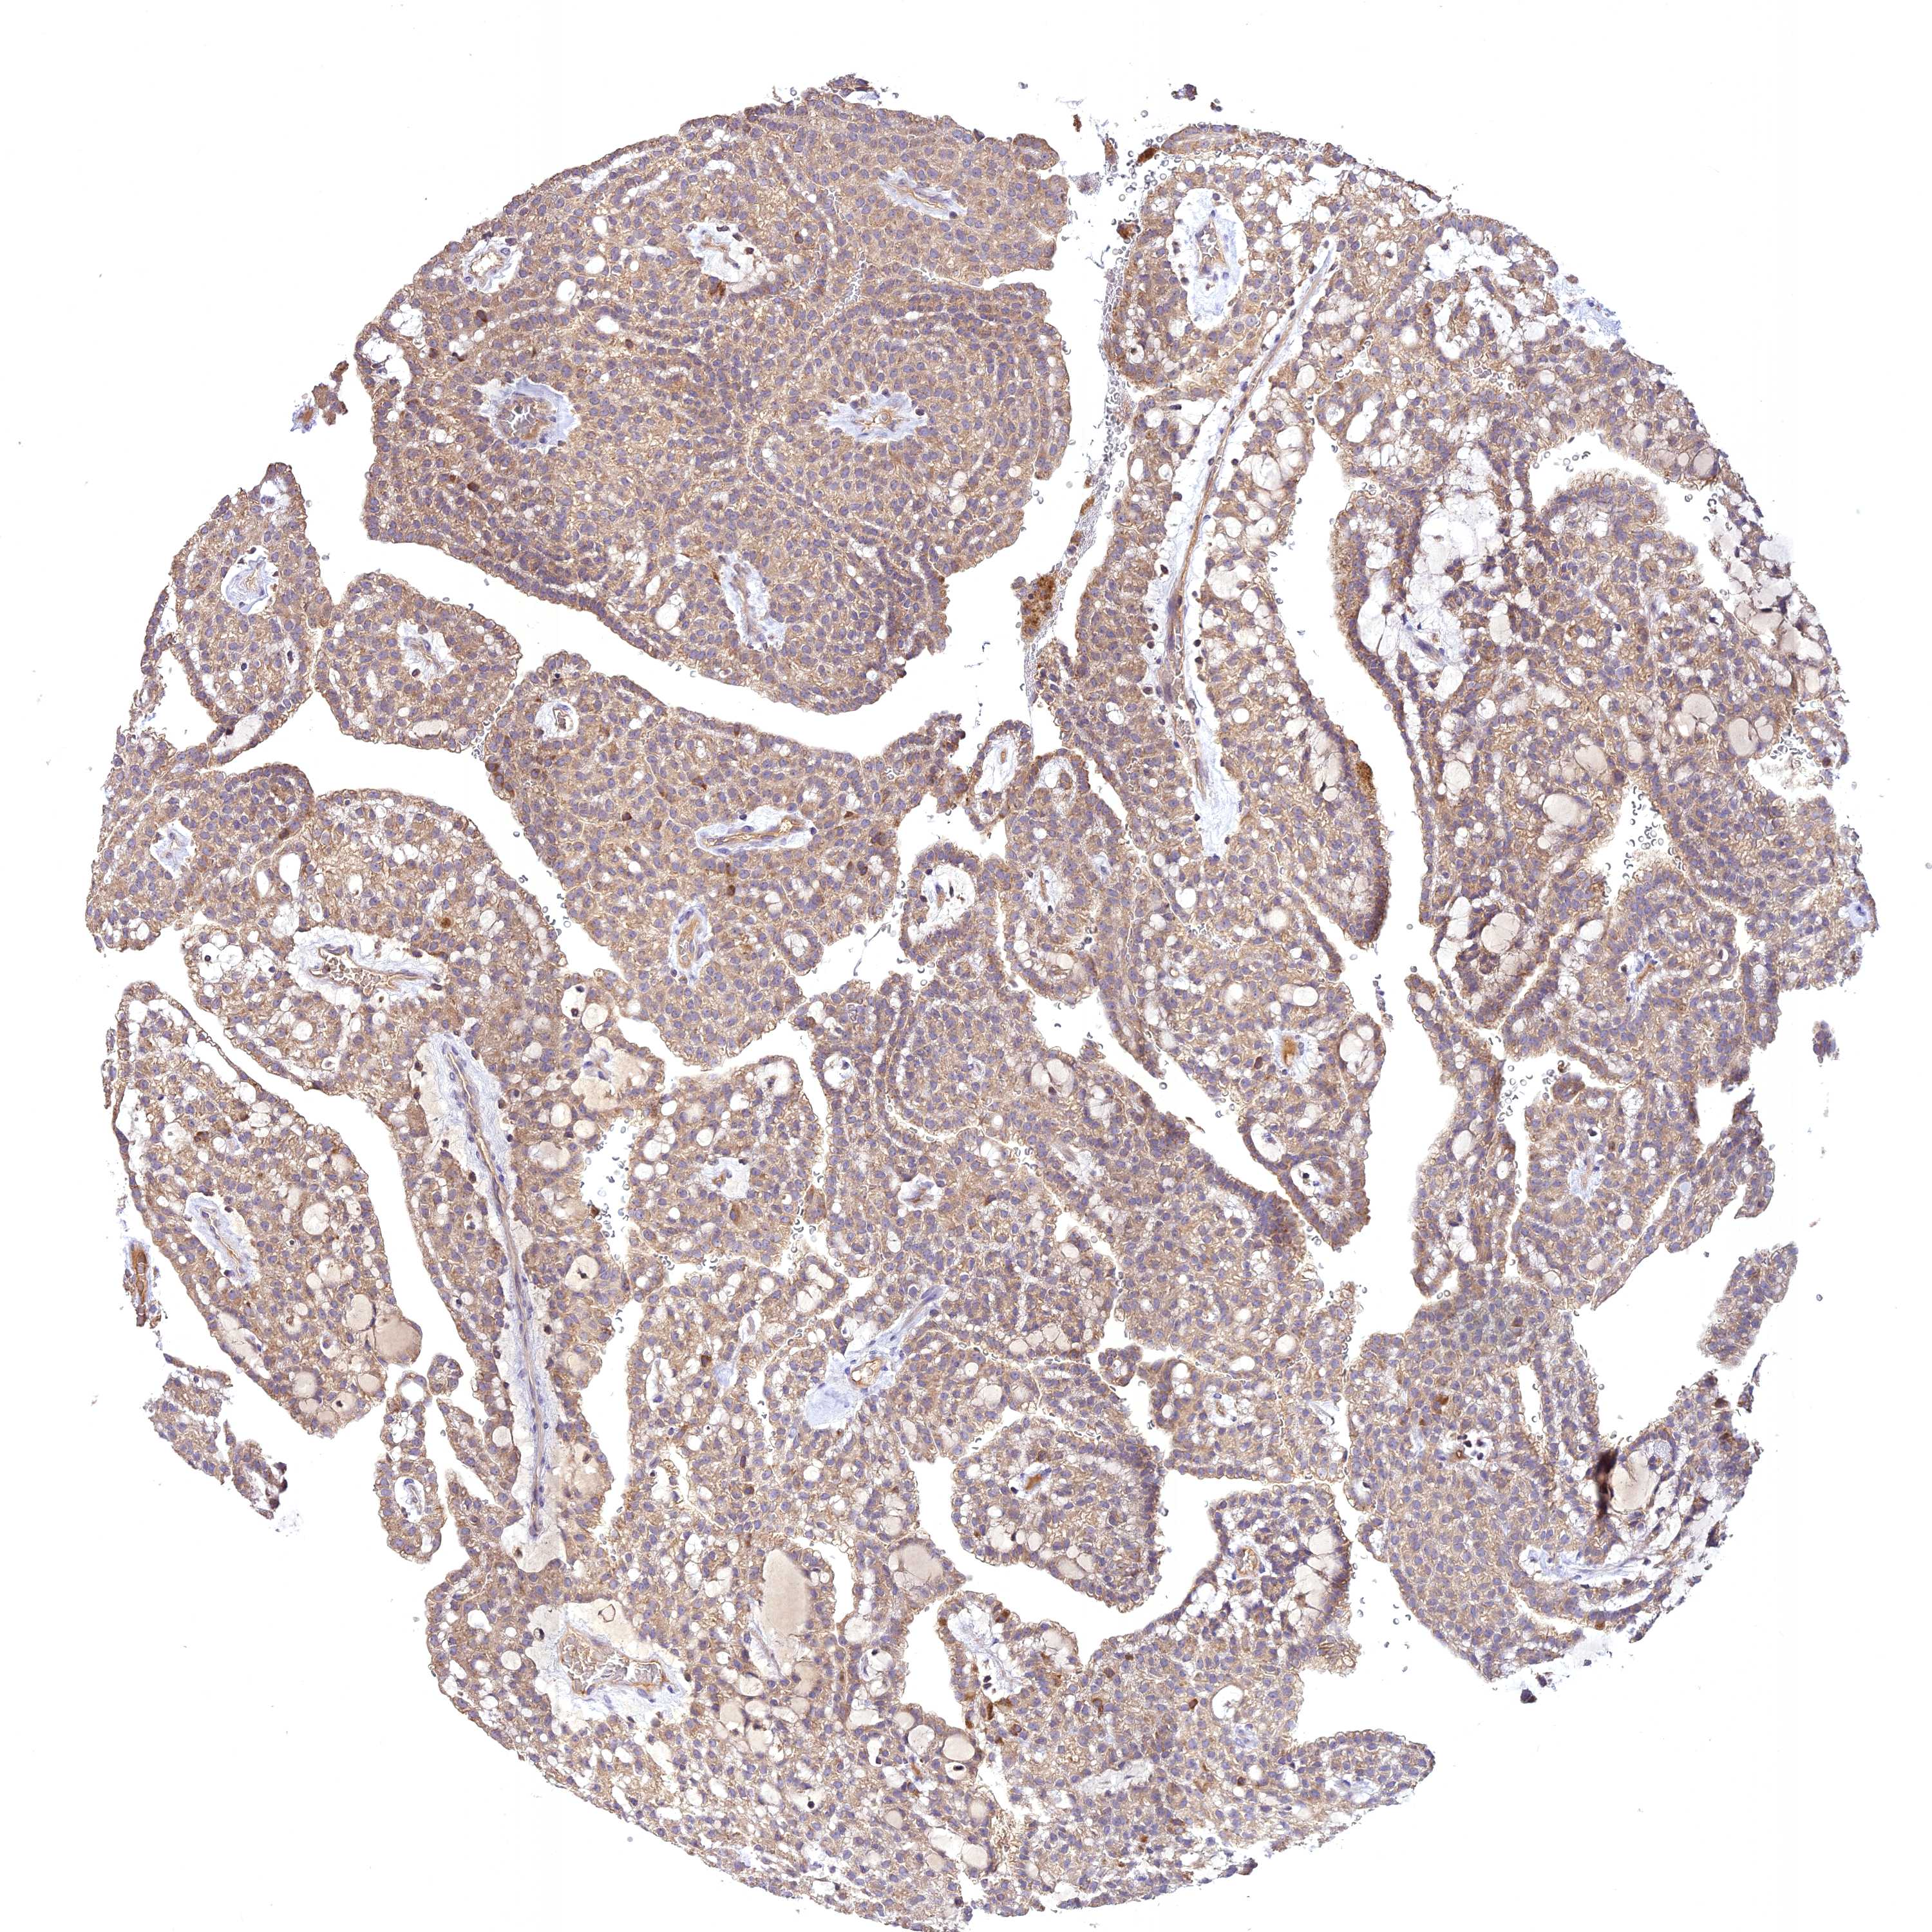

KIDNEY RENAL CLEAR CELL CARCINOMA (VALIDATION) - Interactive survival scatter ploti

The Survival Scatter plot shows the clinical status (i.e. dead or alive) for all individuals in the patient cohort, based on the same data that underlies the corresponding Kaplan-Meier plots. Patients that are alive at last time for follow-up are shown in blue and patients who have died during the study are shown in red.

The x-axis shows the expression levels (FPKM) of the investigated gene in the tumor tissue at the time of diagnosis. The y-axis shows the follow-up time after diagnosis (years). Both axes are complimented with kernel density curves demonstrating the data density over the axes. The top density plot shows the expression levels (FPKM) distribution among dead (red) and alive patients (blue). The right density plot shows the data density of the survived years of dead patients with high and low expression levels respectively, stratified using the cutoff indicated by the vertical dashed line through the Survival Scatter plot. This cutoff is automatically defined based on the FPKM cutoff that minimizes the p-score. The cutoff can be changed by dragging the vertical line or by entering a cutoff value in the square labeled "Current cut-off".

Under the Survival Scatter plot the p-score landscape (black curve; left axis) is shown together with dead median separation (red curve; right axis). Dead median separation is the difference in median mRNA expression between patients who have died with high and low expression, respectively. It is calculated as follows: median FPKM expression of dead patients with high expression - median FPKM expression of dead patients with low expression. This is intended to aid the user in visually exploring custom cutoffs and the associated p-scores and dead median separation.

Individual patient data is displayed and can be filtered by clicking on one or more of the category buttons on the top of the page. Categories describing expression level and patient information include: high, low, alive, dead, female, male and tumor stages. The scale of the x-axis can be toggled between linear and log-scale by clicking on the "x log" button. Mouse-over function shows TCGA ID, patient information and mRNA expression (FPKM) for each patient.

& Survival analysisi

Kaplan-Meier plots summarize results from analysis of correlation between mRNA expression level and patient survival. Patients were divided based on level of expression into one of the two groups "low" (under cut off) or "high" (over cut off). X-axis shows time for survival (years) and y-axis shows the probability of survival, where 1.0 corresponds to 100 percent.

NUDT8 is not prognostic in Kidney Renal Clear Cell Carcinoma (validation)

Best expression cut offi

Based on the FPKM value of each gene, patients were classified into two groups and association between prognosis (survival) and gene expression (FPKM) was examined. The best expression cut-off refers the FPKM value that yields maximal difference with regard to survival between the two groups at the lowest log-rank P-value. Best expression cut-off was selected based on survival analysis .

When clicking on this number, the vertical dashed line indicating cut-off, the interactive survival plot, and the Kaplan-Meier curve will be adjusted to show results based on the best expression cut-off.

: 20.59

Median expressioni

Median expression refers to the median FPKM value calculated based on the gene expression (FPKM) data from all patients in this dataset. When clicking on this number, the vertical dashed line indicating cut-off, the interactive survival plot, and the Kaplan-Meier curve will be adjusted to show results based on the median expression.

: N/A

Median follow up timei

Median follow up time refers to the median time (years) after diagnosis with this type of cancer, based on clinical data from all patients in this dataset.

P scorei

Log-rank P value for Kaplan-Meier plot showing results from analysis of correlation between mRNA expression level and patient survival.

N/A

5-year survival highi

5-year survival for patients with higher expression than the expression cutoff.

For melanoma and glioma, 3-year survival is shown.

5-year survival lowi

5-year survival for patients with lower expression than the expression cutoff.

TCGA RNA samplesi

RNA-seq data is reported as average FPKM (number Fragments Per Kilobase of exon per Million reads), generated by the The Cancer Genome Atlas (TCGA) .

Normal distribution across the dataset is visualized with box plots, shown as median and 25th and 75th percentiles. Points are displayed as outliers if they are above or below 1.5 times the interquartile range. FPKM values of the individual samples are presented next to the box plot.

Average pTPM 15.7

Number of samples 100